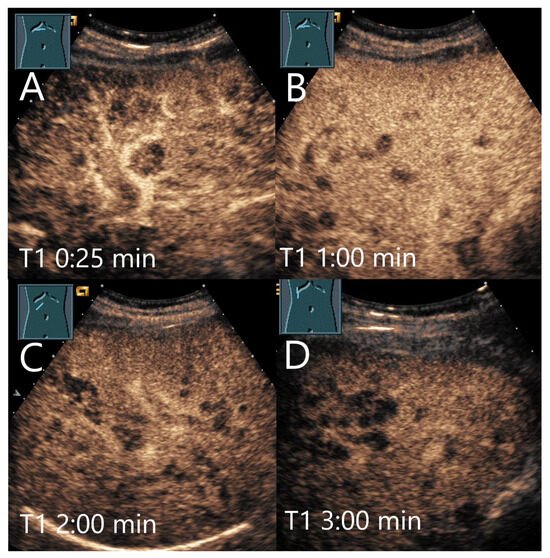

Figure 14.

Sarcoidosis. Female patient with multiple hypoechoic liver lesions up to 10 mm. The CEUS shows after 25 s (A), 1 min (B), 2 min (C), and after 3 min (D) a progressive hypoenhancement. The US-guided biopsy revealed a diagnosis of hepatic sarcoidosis.